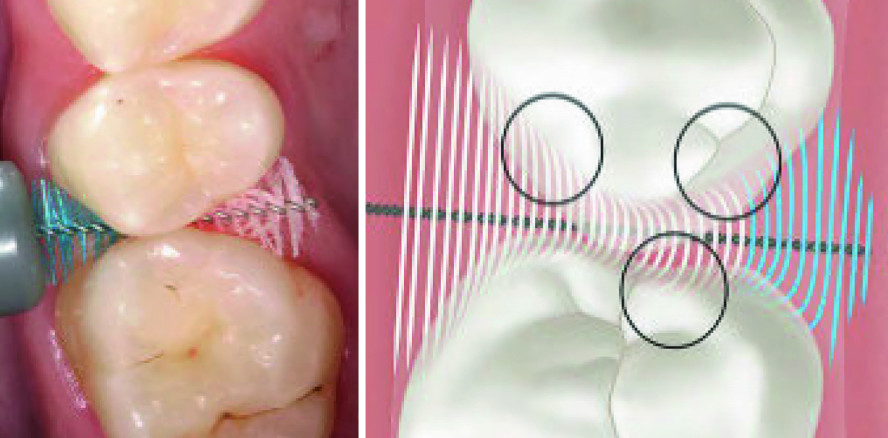

Abb. 2: Eine richtige Bürstengröße ermöglicht eine effiziente Biofilmentfernung in den Zahnzwischenräumen. Dieses Schema zeigt, dass mit der verwendeten Bürste gewisse Oberflächen nicht erreicht werden. Die Biofilmentfernung ist unvollständig. © Dr. Thomas Jaeggi, Prof. Dr. Adrian Lussi

Abb. 4: Studien haben gezeigt, dass die Biofilmentfernung durch IDB mit konkavem Borstendesign besser ist. Die konkave Bürste erreicht die schwer zugänglichen Zahnoberflächen besser. © Dr. Thomas Jaeggi, Prof. Dr. Adrian Lussi